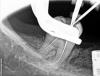

BORA Опубликовано 30 апреля, 2011 Поделиться Опубликовано 30 апреля, 2011 ...депульпировали...недолет....поправка....латералка... Ah+..чужой в апексе?! Ссылка на комментарий

BORA Опубликовано 30 апреля, 2011 Автор Поделиться Опубликовано 30 апреля, 2011 неплохо для имплантолога! терапевт...сползающий на ортопедию и имплантологию)))) ...на снимке не мои имплантаты..тутесли присмотреться расщепление делали......на моем счету только парочка)) Ссылка на комментарий

Scrabble Опубликовано 30 апреля, 2011 Поделиться Опубликовано 30 апреля, 2011 файлы -про-эндопротейперы-ручныемту-20 скребсяВы за такие изгибы протейперами пролезли?? Ссылка на комментарий

Dzekhmd Опубликовано 1 мая, 2011 Поделиться Опубликовано 1 мая, 2011 ...депульпировали...недолет....поправка....латералка... Ah+..чужой в апексе?! Мдя... Еще раз убеждаюсь, нет ничего невозможного Браво Сколько времени ушло на обработку? Ссылка на комментарий